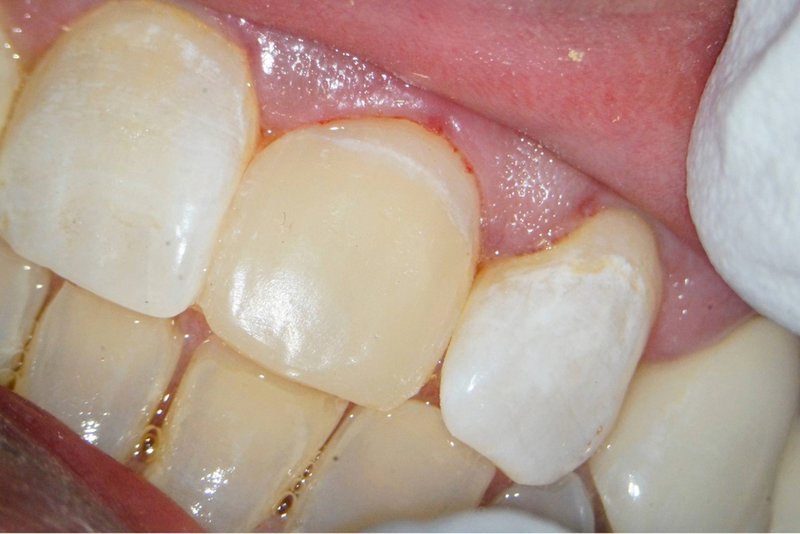

Kronenfraktur: Zustand vor der Wurzelkanalbehandlung